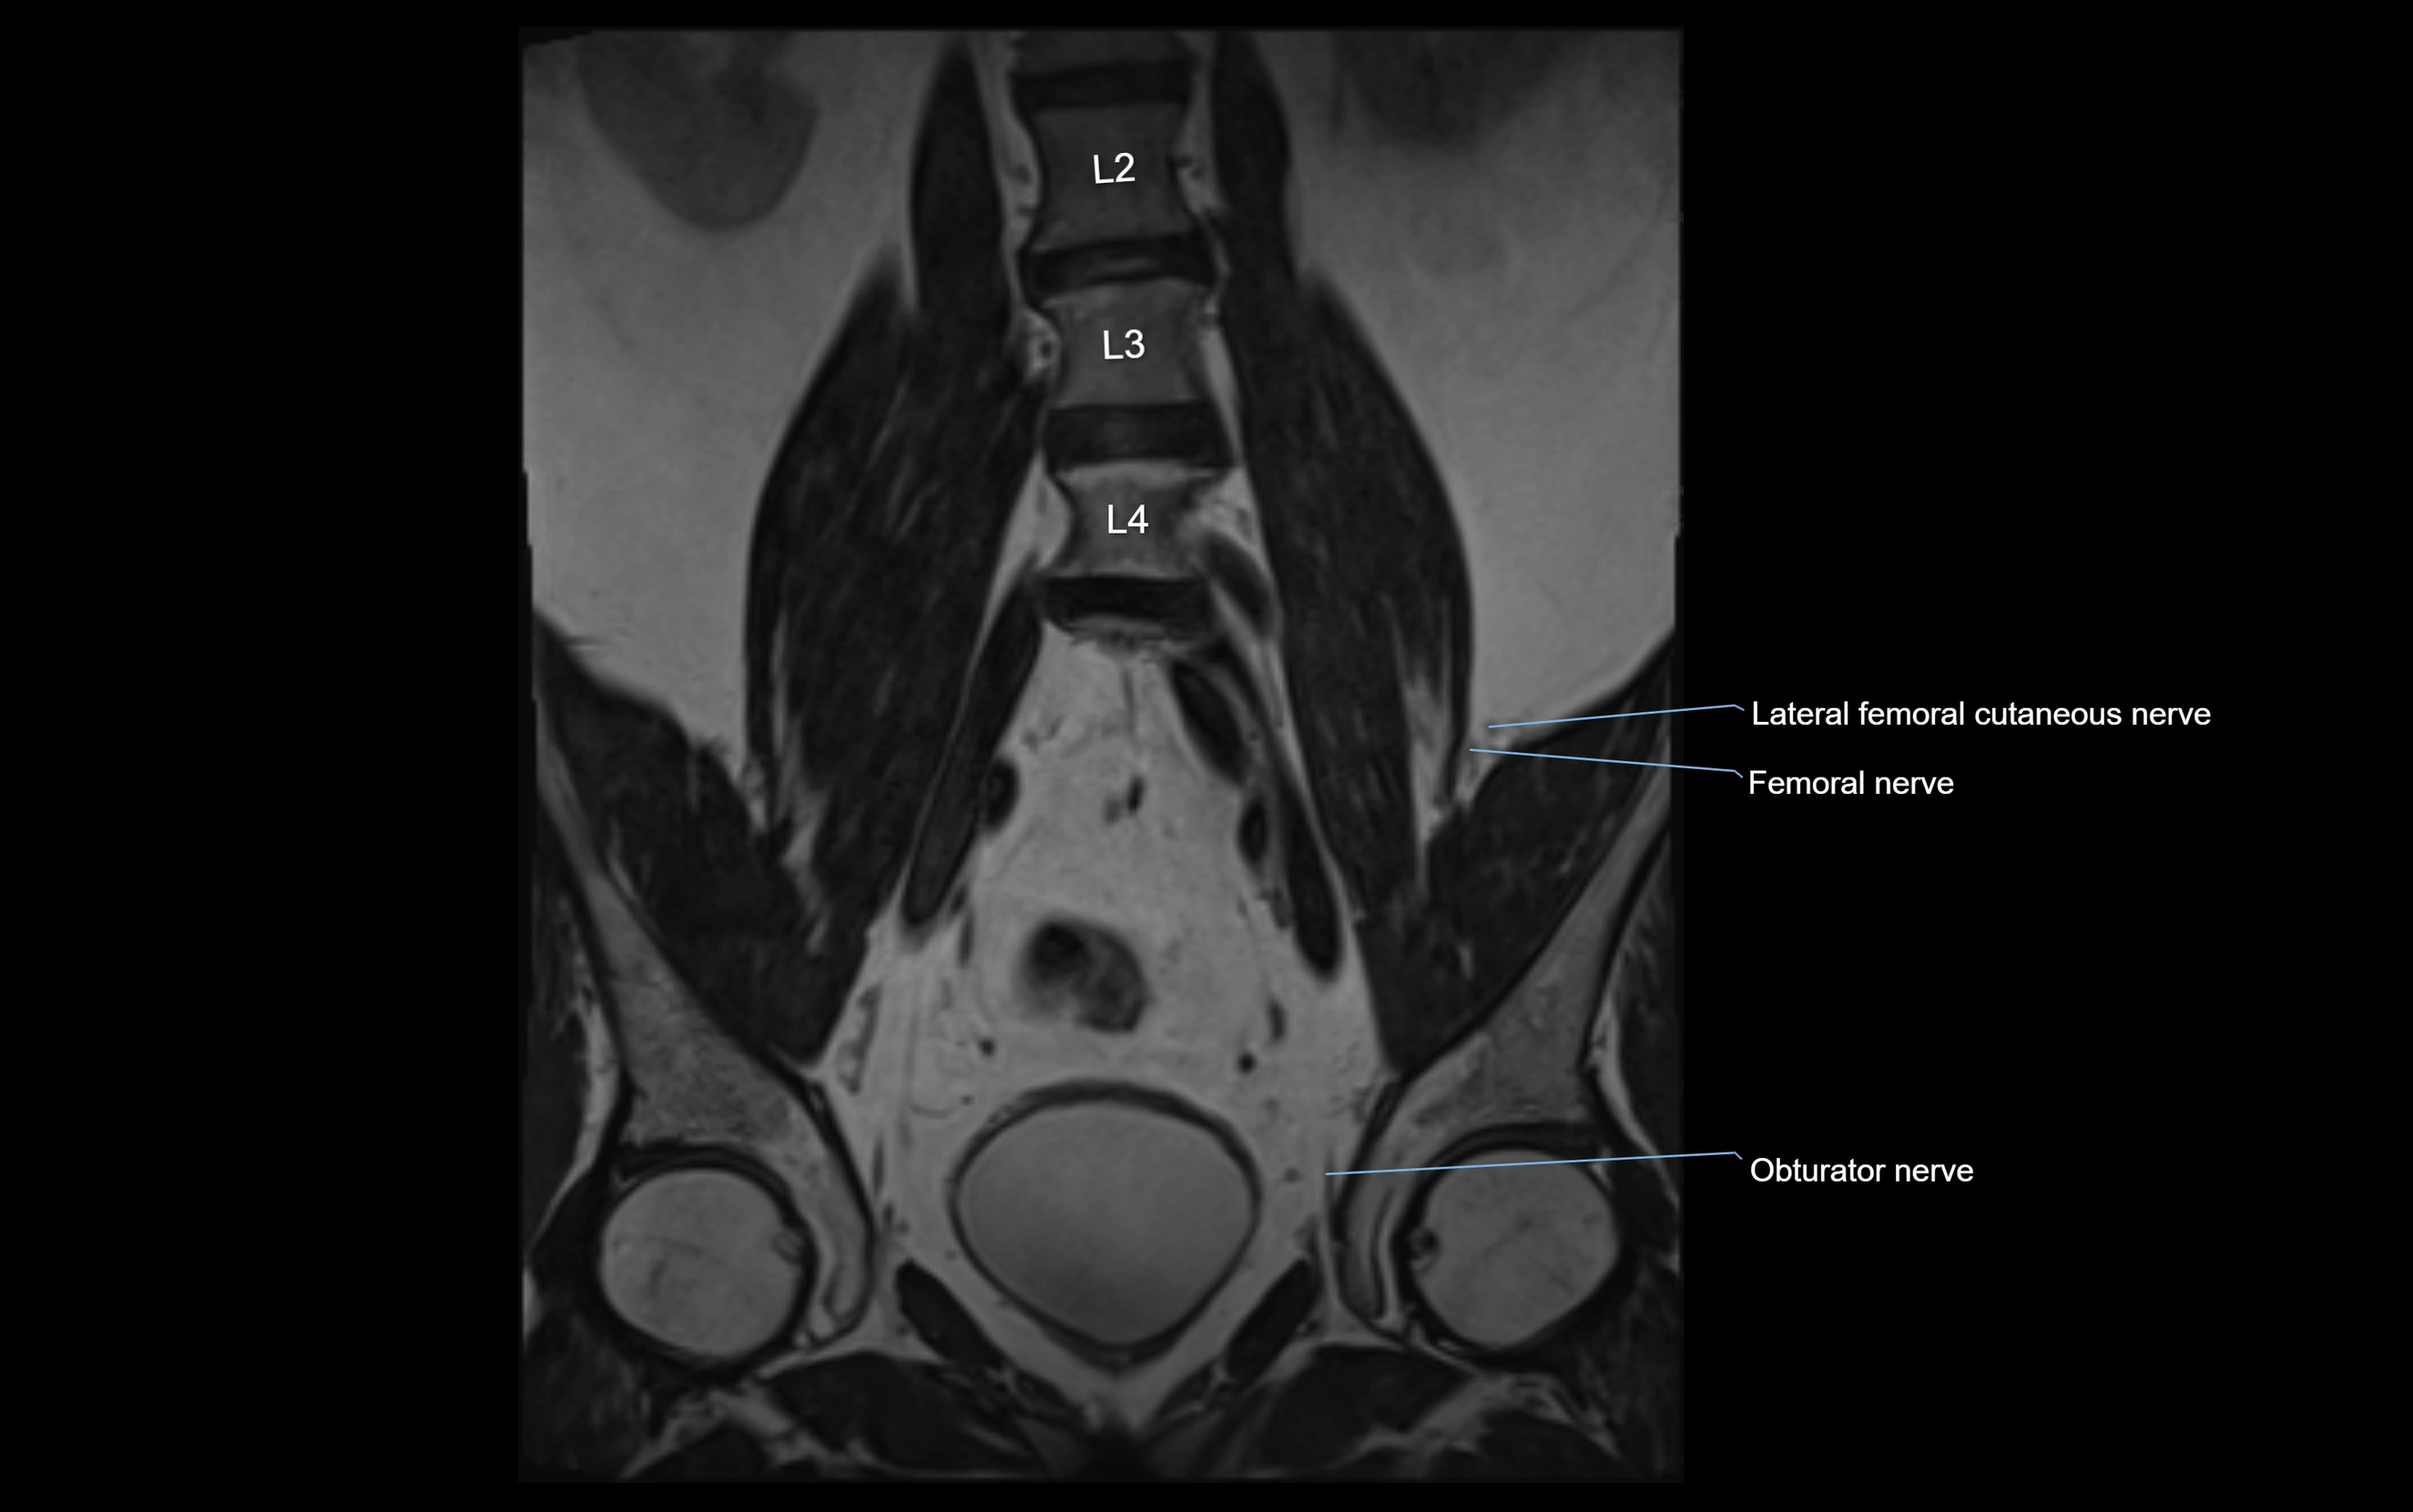

MRI image

image